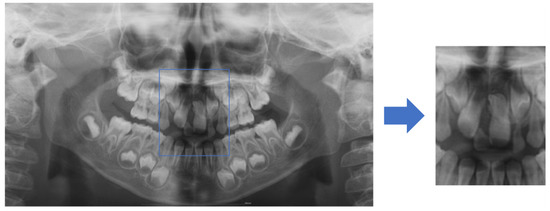

2.3.1. Data Preprocessing

2.3.2. Data Classification